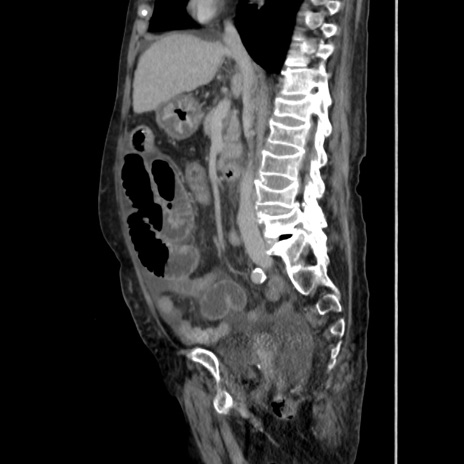

症例31(矢状断像)

【症例】80歳代 女性

【主訴】腹部膨満感

【現病歴】他院にて肝硬変にてフォロー中。1週間前から便秘、腹部膨満感、臍部腫瘤あり受診となる。

【既往歴】肝硬変

【身体所見】腹部膨隆あり、皮膚変化なし、疼痛なし。

【データ】WBC 4600、CRP 0.25